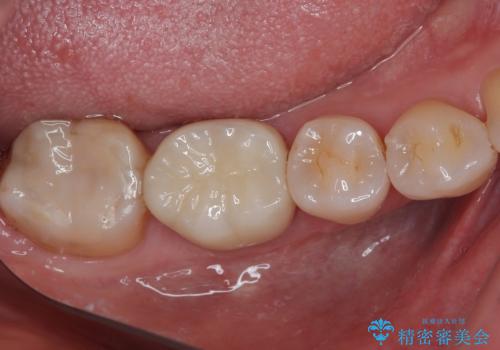

適合もよく、機能的に問題もなく、見た目も満足されていました。